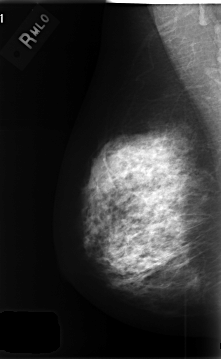

C_0412_1.RIGHT_MLO

RIGHT_MLO LINES 4656 PIXELS_PER_LINE 2864 BITS_PER_PIXEL 12 RESOLUTION 50 NON_OVERLAY